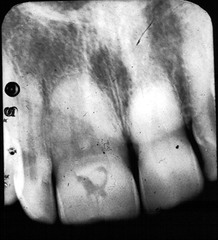

-obstruction in the gland hard nodule in soft tissue at a salivary gland -calcification of material -can be seen radiographically